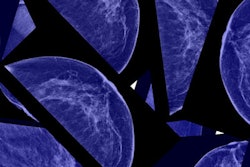

Nancy's original diagnosis came as a shock to her, especially as she had complied with breast screening guidelines and received several normal mammograms. Her stage IIIC breast cancer was found via clinical breast examination as a 2.5-cm lump.

But even more shocking to Nancy was the reaction of her healthcare providers. She was told that it was common knowledge that conventional x-ray mammography didn't work well in women with dense breast tissue -- such as hers. Despite this knowledge, Nancy was never referred for supplemental imaging, such as ultrasound or breast MRI.